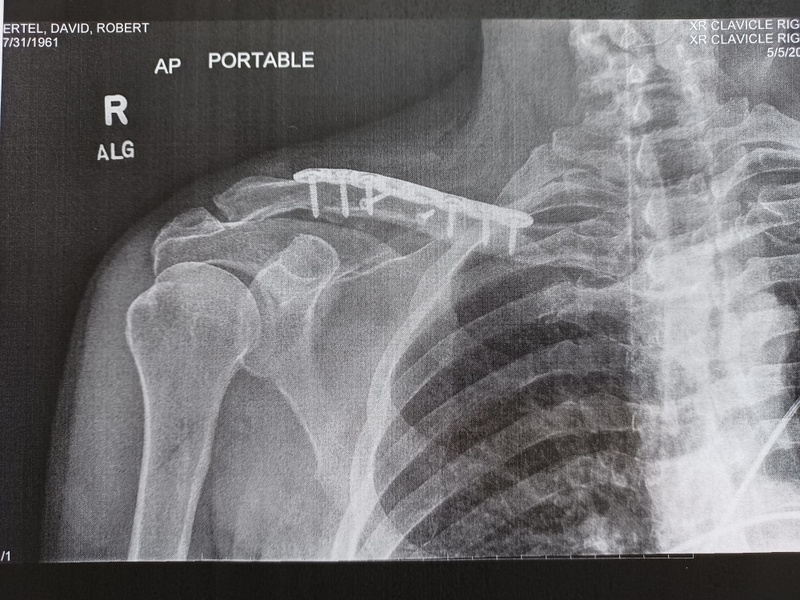

At the hospital, they confirmed the break. It was Sunday so they couldn’t do much more. They sent me home with some drugs and a sling. I had a follow-up meeting with an orthopaedic surgeon on Wednesday and then surgery on Thursday. These days they only insert plates in collarbones that have compound breaks. Mine was a “z” compound fracture – not good – I needed a plate. Without surgery, one of my arms would have been about an inch shorter than the other, easy call, get the surgery. Post operation, I now have a plate and 8 screws in my collarbone. For the record Nancy has a plate and 11 screws in her collarbone so she must have broken hers worse than I did.

The accident was on May 1st and my surgery was on May 5th., Right now I feel like I’m doing pretty well. I’ve had no pain since surgery; I’m sleeping well and can move my wrist and elbow without issue. I have a follow up with the orthopaedic surgeon next week and hope to start therapy soon after. It all depends on the bone healing and only an x-ray can reveal progress there. Riding may be slightly curtailed this year but getting the recovery right is most important now.